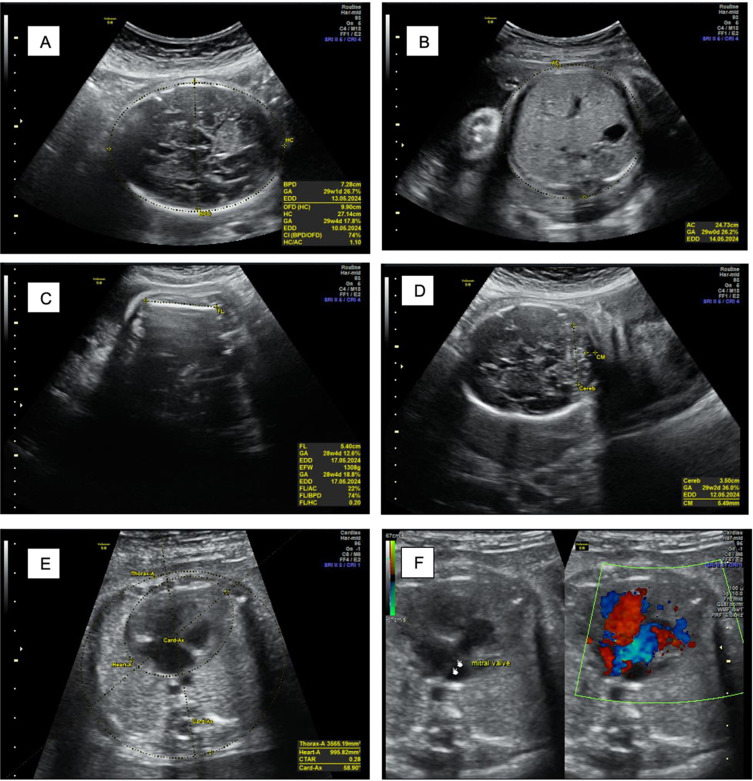

Objective: Atrioventricular block (AVB) is one of the most common causes of fetal bradyarrhythmia. This case highlights a misdiagnosis of fetal bradyarrhythmia as fetal distress and underscores the importance of accurately distinguishing fetal bradycardia from fetal distress through precise prenatal evaluation.

Case report: A 33-year-old pregnant woman was referred to a tertiary care center after an initial diagnosis of suspected fetal distress at a local hospital. Due to limited resources and qualified clinicians to perform accurate diagnosis, further evaluation at the primary facility was not possible. Upon arrival at the tertiary center, one week later, fetal echocardiography was performed. The fetal heart rate was found to be persistently low at 60-70 beats per minute. Fetal echocardiography confirmed the presence of congenital heart disease along with a diagnosis of fetal bradyarrhythmia, most likely due to atrioventricular block.

Conclusion: Fetal bradycardia may indicate the presence of congenital heart disease or conduction abnormalities such as AV block. Accurate diagnosis using fetal echocardiography is essential to distinguish true bradyarrhythmia from non-specific signs of fetal distress and guide appropriate management.